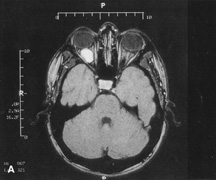

Magnetic resonance imaging is useful in selected cases, especially when evaluating the orbital cranial junction. Significant bony artifact and a lack of orbital fat in the orbital apex make CT scan resolution of the orbital apex structures poor. Because cortical bone has low signal on MRI, there is no bone artifact when viewing the orbital apex on MRI. The lack of intervening fat in the apex to provide contrast is overcome on MRI because contrast is provided by the individual nuclear characteristics of each tissue so that the orbital apex structures are visualized well. Consequently, conditions that affect the optic nerve and chiasm, such as optic nerve meningioma and glioma, generally are evaluated with MRI rather than CT scan (Fig. 2).

Fig. 2. A. Axial orbital CT scan of right optic nerve meningioma. Note lack of detail in orbital apex. B. Axial orbital MR image, same patient. Note increased detail in orbital apex owing to lack of bone artifact. C. MRI with gadolinium contrast. Note extension into brain not easily appreciated with CT scanning or MRI without contrast.

Use of a contrast agent such as gadolinium can further enhance the T1 signal intensity of lesions and is particularly helpful in imaging areas where there has been a breakdown in the blood–brain barrier. Because orbital fat produces a bright signal on T1-weighted images, orbital MR usually is performed with “fat suppression” to prevent masking of lesions. However, incomplete fat suppression can produce artifacts that may be misinterpreted as abnormal enhancement.

A few other orbital conditions are better visualized with MRI than CT scanning.1–3 Often, organic foreign bodies, such as wood, are not imaged well with CT scan. These foreign bodies often are visible with MRI. However, care must be taken when imaging any metallic intraocular or intraorbital foreign body because the strong magnetic field of the MR scanner may cause the foreign body to shift position and damage surrounding structures. In some tumors and vascular anomalies, high blood flow is appreciated on MRI. This is caused by a lack of signal, known as a flow void, created by blood flowing rapidly through larger vessels. Tumors that originate in the brain and extend into the orbit secondarily, such as sphenoid wing meningioma, also are visualized well with MRI. However, bony detail and calcification within the meningioma are not imaged well. In unusual circumstances such as this, CT scan and MRI may prove to be complementary, and both techniques may be required to fully evaluate the orbital disease process.